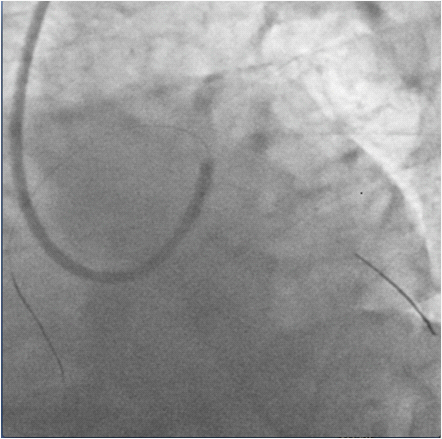

The patient was wheeled into the catch lab after pre-loading with 60mg Prasugrel and 300mg of Aspirin. He received 7,500units of unfractionated heparin and underwent coronary angiography from the right femoral route, which revealed 70% distal left main (LM) stenosis, and 70-80% ostial blocks of the left anterior descending (LAD) and left circumflex (LCX) arteries (Figures 2 & 3), (Video 1).The right coronary artery had a 50% stenosis at mid level (Figure 4). The patient was continuing to have chest pain despite prior administration of intra-venous morphine in the ER. He however was in a position to give informed consent for primary percutaneous intervention (PCI) subsequent to explaining that PCI would be a viable alternative keeping in view the urgency of intervention in his condition.

Figure 2 Coronary angiogram in right anterior oblique caudal view showing tight distal left main and ostial left anterior descending coronary arteries stenosis.